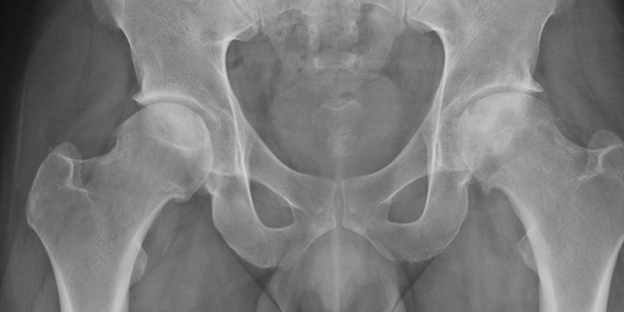

Avascular Necrosis of the Femoral Head

Diagnosing AVN can be difficult because there are no distinguishing clinical features about the disease. History may reveal predisposing risk factors in the patient with non traumatic hip pain which may initiate suspicion. AVN can be asymptomatic for more than 5 years. Often pain is gradual and insidious in onset, although some report a moment when acute pain began. On physical exam, pain is around the groin or hip (or affected joint), but may sometimes radiate to the buttocks, knee or anteromedial thigh. If around the hip joint, the pain can be elicited with standing and eased with rest. Range of motion testing is painful.